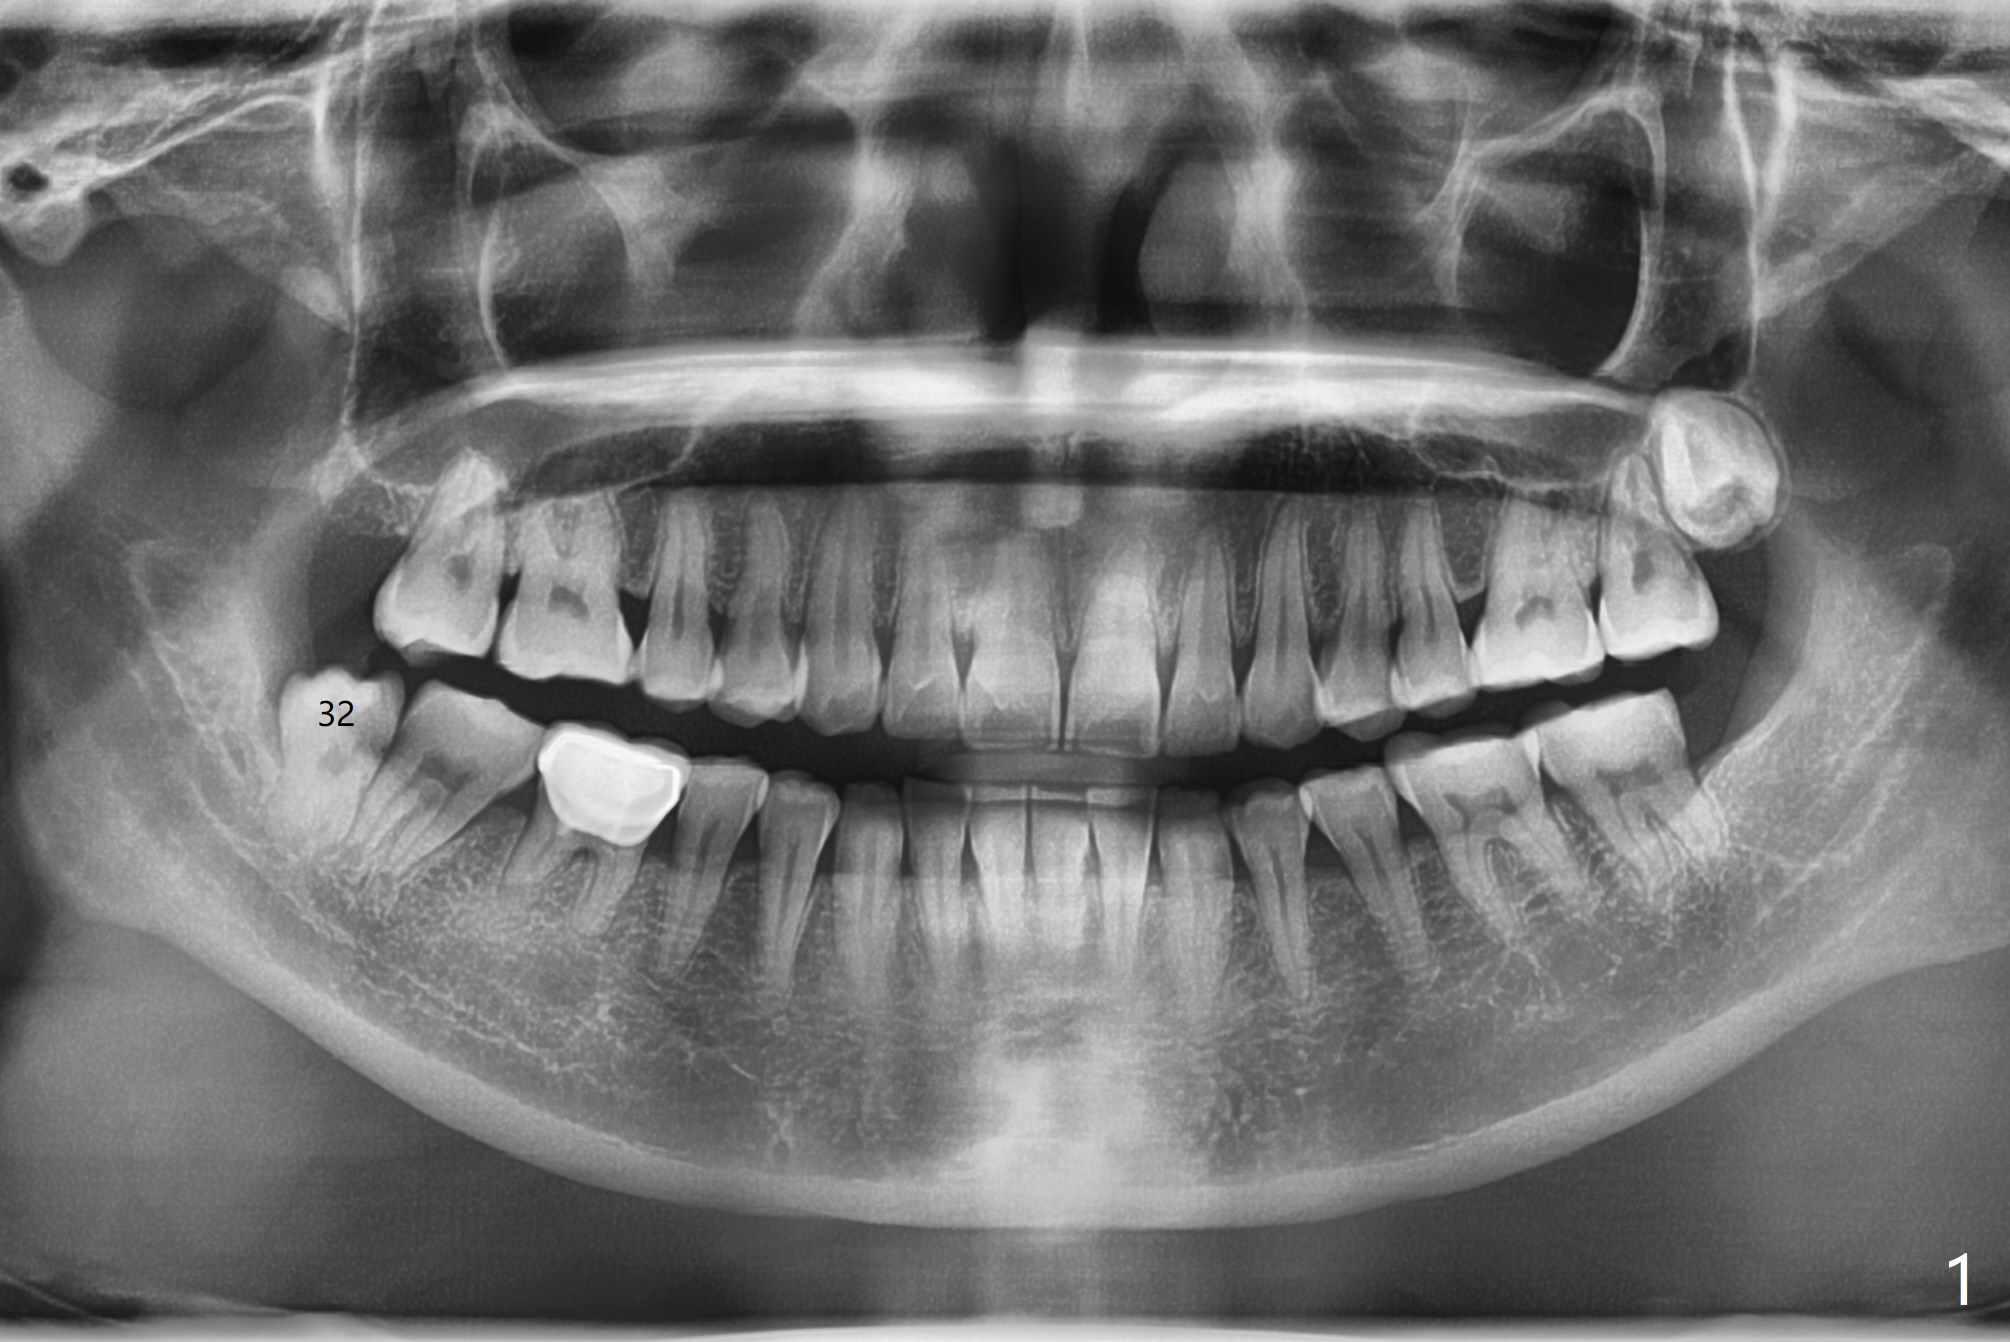

A 37-year-old woman requests extraction of the tooth #32 (Fig.1,2 (< cheek bite)). Note no bone between the last 2 molars. The tooth is extracted with incision, but without bone removal. Vanilla graft (Fig.3 *) is placed as mesial as possible, while Osteogen plug (P) coronal before suturing. The white dashed line in Fig.4 most likely represents the mesial wall of the 3rd molar socket (fused roots). The distal root of the 2nd molar seems to be partially covered by the bone.